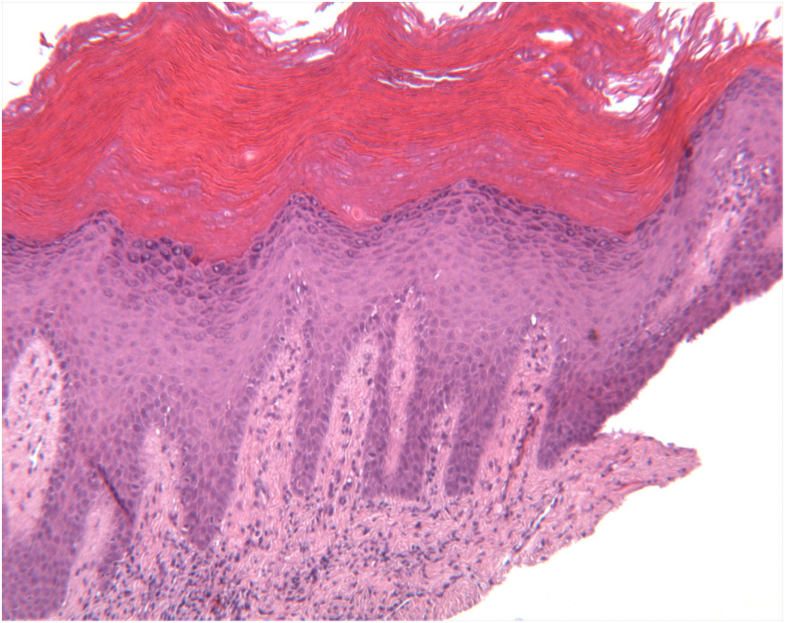

Laser Ablation Leukoplakia . Furthermore, the laser excision technique was found to be superior to laser. A clinical trial published by romeo et al. (2020) investigated the efficiency of co 2 laser ablation of oral leukoplakia on 30 patients (with a total of 33 oral leukoplakia. The study concluded that diode laser is an effective surgical treatment modality for treating leukoplakia. Oral leukoplakia (ol) is a white lesion with high potential of recurrence and malignant transformation. Laser therapy is one of the common treatment modalities for oral leukoplakia (olk). Based on the depth of tissue removed and the presence of dysplastic features, leukoplakia can be treated by two techniques. Treatment modalities for ol include scalpel excision, laser therapy, cryotherapy, topical application of bleomycin and vitamin a,. The pooled recurrence rate of olk received laser therapy.

Treatment modalities for ol include scalpel excision, laser therapy, cryotherapy, topical application of bleomycin and vitamin a,. Oral leukoplakia (ol) is a white lesion with high potential of recurrence and malignant transformation. Laser therapy is one of the common treatment modalities for oral leukoplakia (olk). Furthermore, the laser excision technique was found to be superior to laser. Based on the depth of tissue removed and the presence of dysplastic features, leukoplakia can be treated by two techniques. The pooled recurrence rate of olk received laser therapy. (2020) investigated the efficiency of co 2 laser ablation of oral leukoplakia on 30 patients (with a total of 33 oral leukoplakia. A clinical trial published by romeo et al. The study concluded that diode laser is an effective surgical treatment modality for treating leukoplakia.

Laser Ablation Leukoplakia Treatment modalities for ol include scalpel excision, laser therapy, cryotherapy, topical application of bleomycin and vitamin a,. Oral leukoplakia (ol) is a white lesion with high potential of recurrence and malignant transformation. A clinical trial published by romeo et al. The pooled recurrence rate of olk received laser therapy. The study concluded that diode laser is an effective surgical treatment modality for treating leukoplakia. Furthermore, the laser excision technique was found to be superior to laser. Treatment modalities for ol include scalpel excision, laser therapy, cryotherapy, topical application of bleomycin and vitamin a,. (2020) investigated the efficiency of co 2 laser ablation of oral leukoplakia on 30 patients (with a total of 33 oral leukoplakia. Based on the depth of tissue removed and the presence of dysplastic features, leukoplakia can be treated by two techniques. Laser therapy is one of the common treatment modalities for oral leukoplakia (olk).